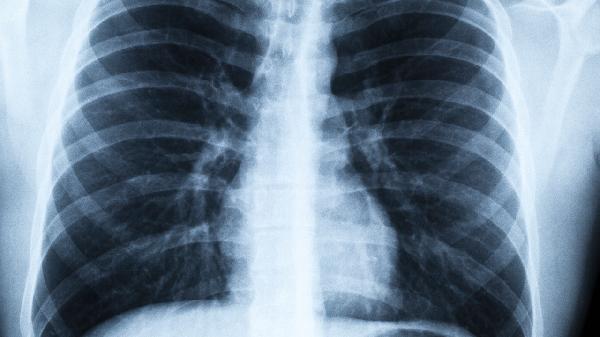

病毒性肺炎是由病毒感染引起的间质性炎症,病理表现为肺泡壁充血水肿和淋巴细胞浸润。化脓性炎症则由细菌感染导致,特征为中性粒细胞浸润和脓液形成,两者在病原体和病理改变上存在本质区别。